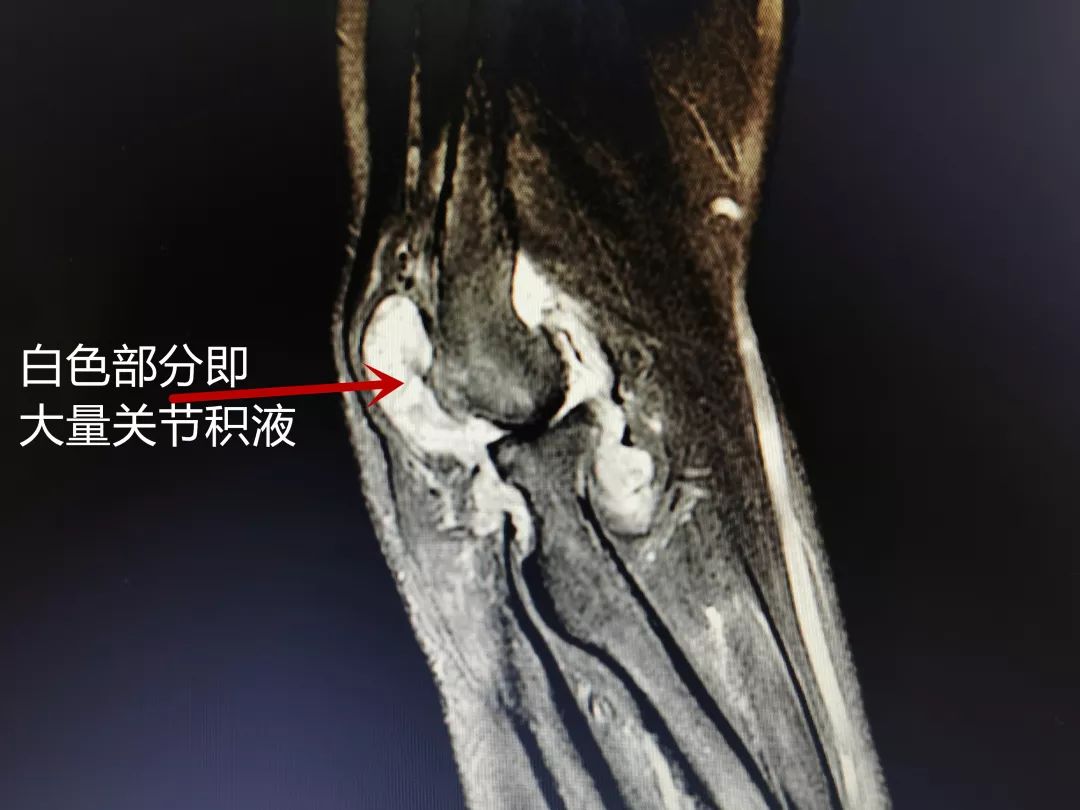

肘关节积液

滑膜出现增生,软骨受到损伤,张大妈的肘关节腔内有大量炎性积液;"我的